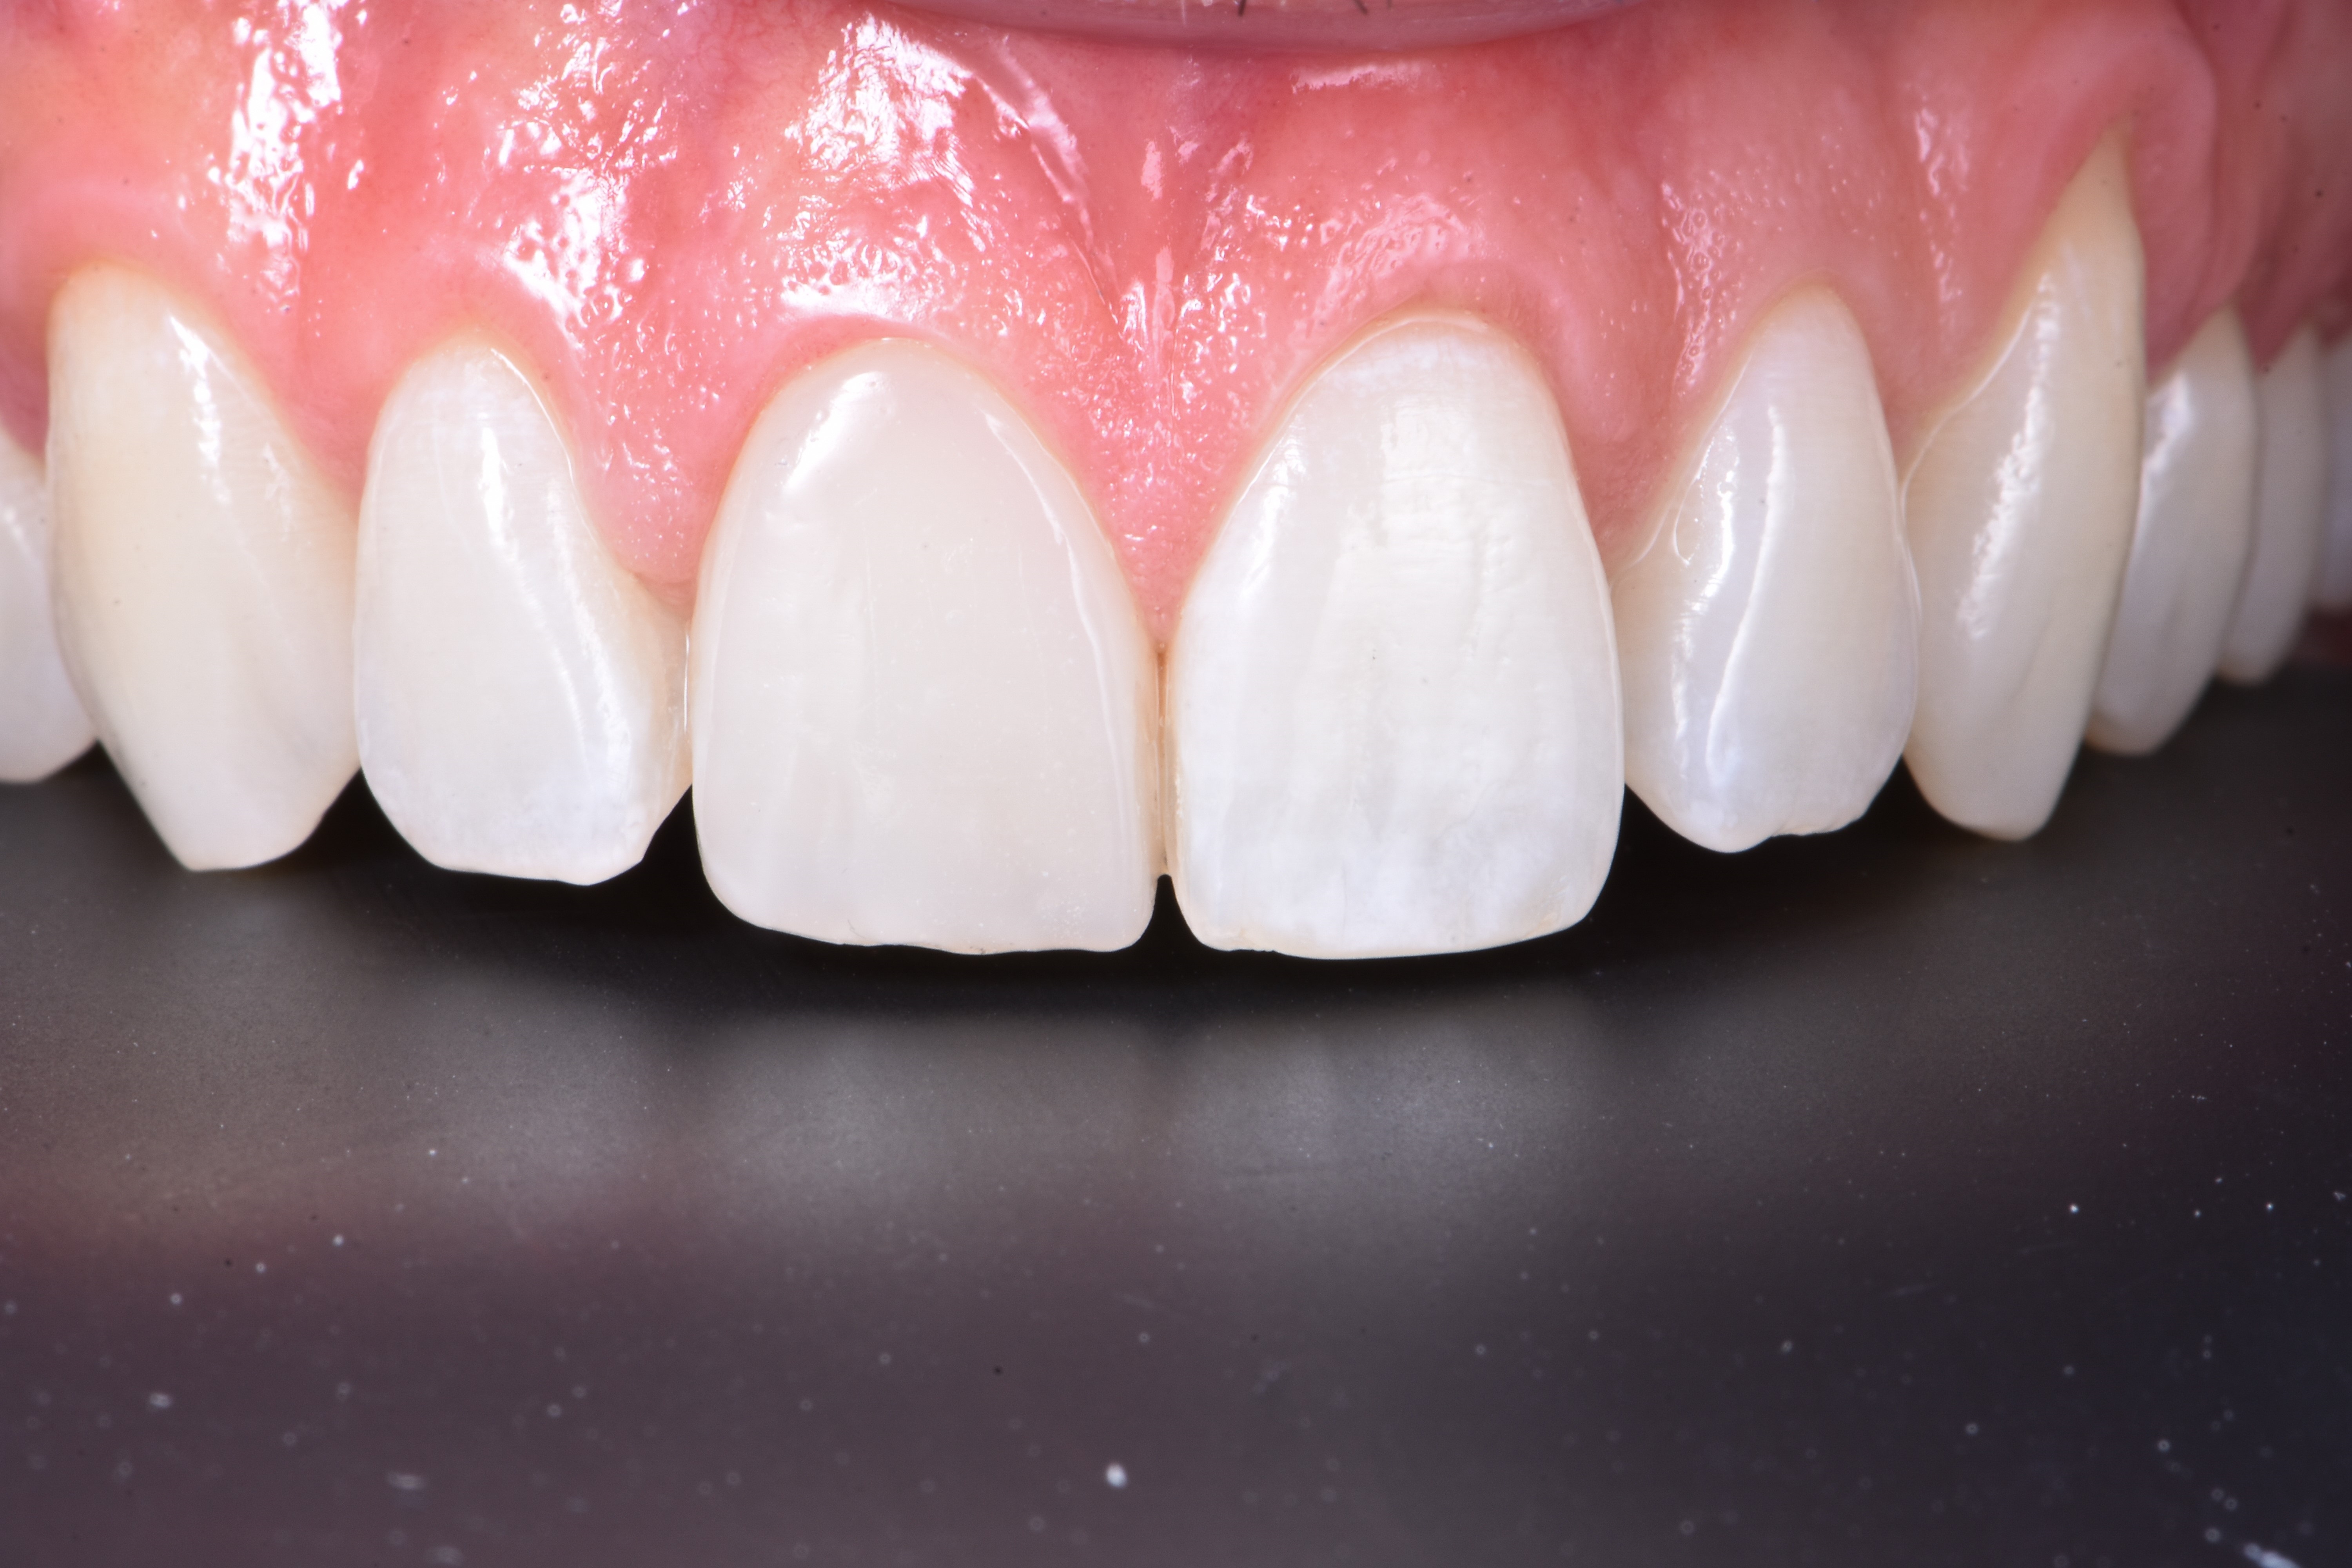

Korona zęba 11 była przebarwiona i ustawiona bardziej podniebiennie w porównaniu z koroną zęba sąsiedniego, tj. zęba 21 (ryc. 2).

Analiza estetyczna wykazała asymetrię położenia zenitów dziąsła między zębami 11 i 21. Po wykonaniu znieczulenia, z użyciem sondy periodontologicznej potwierdzono zaburzone bierne wyrzynanie typu 1A według klasyfikacji Cosleta i wsp. (1).